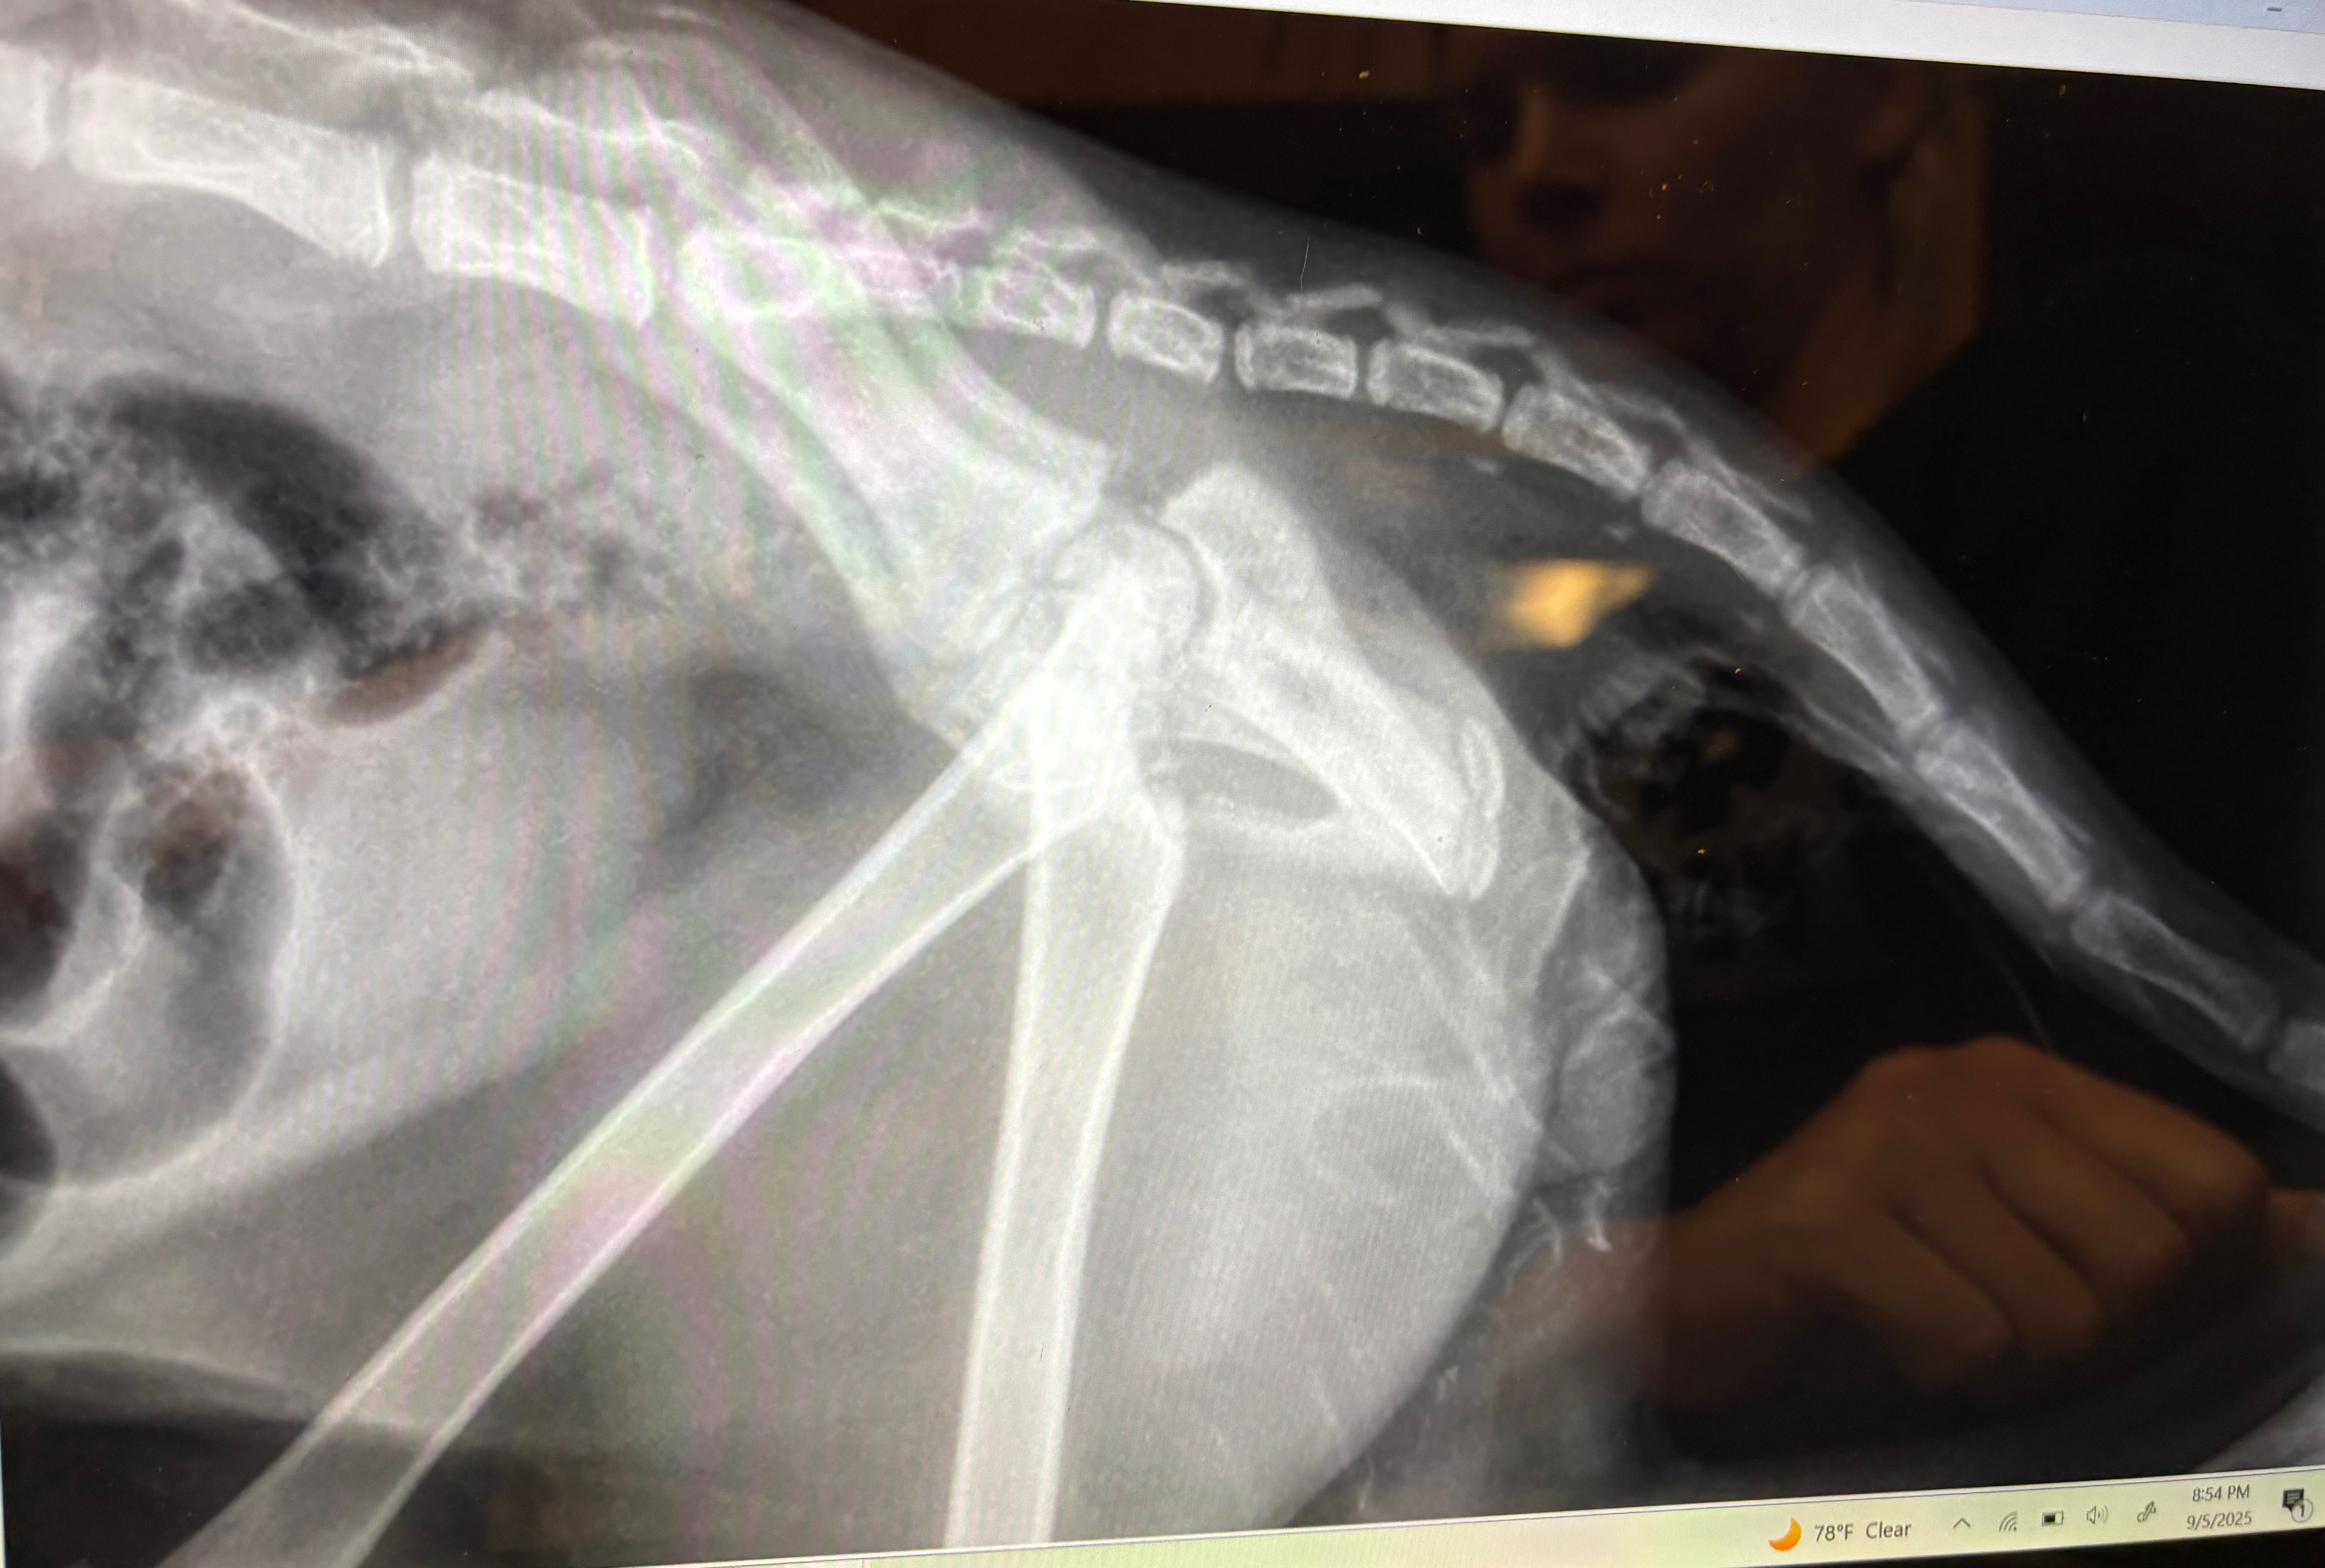

Despite being only 6 months old, Astro tried to escape and defend himself. However, the adult dog caught him, bit him, and broke the bone in his right pelvis, as well as causing other injuries. Agustín intervened and was able to free Astro.

According to the veterinarian at the emergency hospital and an orthopedic surgeon, Astro needed a fracture repair procedure on his long bone to help him live better.

On September 10, Astro went to Fusion Veterinary Orthopedics in Lanham, Maryland. The surgery was successful, and Astro is now in the midst of a three-month recovery process.